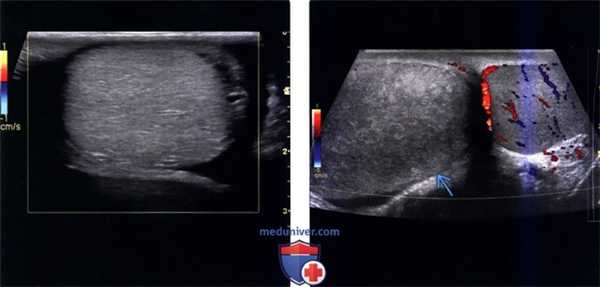

(Слева) Цветовое допплеровское картирование, поперечная плоскость, левое яичко, мужчина с острой болью в мошонке в течение двух часов: полное отсутствие внутреннего потока. Обратите внимание на нормальный гомогенный вид паренхимы в В-режиме, что говорит о потенциальной жизнеспособности яичка.

(Справа) Цветовое допплеровское картирование обоих яичек, поперечная плоскость: определяется увеличенное гетерогенное аваскулярное правое яичко с аномальной линией. Симптомы сохраняются у пациента в течение 24 часов; яички не могут быть жизнеспособными после деторсии.